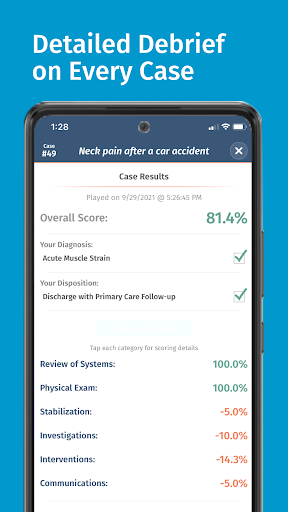

• Điểm số chi tiết và phân tích toàn bộ trường hợp - tìm hiểu điểm mạnh và điểm yếu của bạn

Các trường hợp có thể lặp lại vô hạn của Full Code đo lường các kỹ năng trong cả chẩn đoán và quản lý, cho phép bạn học hỏi từ những sai lầm của mình trong một môi trường không có rủi ro. Xây dựng năng lực để bạn có thể đối mặt với các trường hợp thực tế phức tạp một cách tự tin.